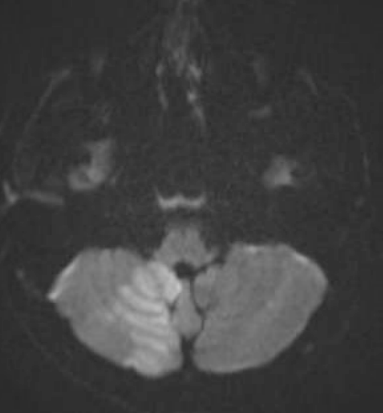

Two days later, he returned with right facial numbness and dysarthria and was found to have a right cerebellar stroke. TTE showed the mass to be larger and more mobile. A DNA sequencing culture from his prior admission was positive for Aspergillus. His B-1,3-D-glucan level was elevated. A CT chest showed nodular opacities consistent with fungal infection. An US of his right arm showed a septic abscess. He was diagnosed with Aspergillus endocarditis and valvulopathy with embolic features. He was started on micafungin and voriconazole. Due to induction failure, he was not a candidate for cardiovascular surgery. His B-1,3-D-glucan level downtrended. He sustained a second Left MCA stroke, emboli to his extremities, erosion of his pulmonary artery, and passed away three months after initial presentation.